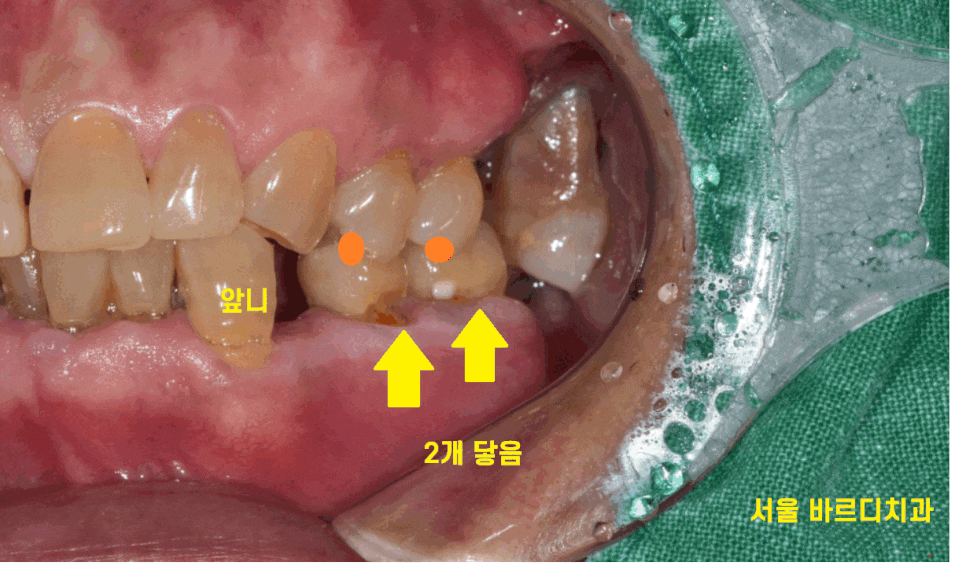

그러다 보니 씹을 수 있는 치아가

몇 개 없었습니다.

치아는 있어도 문제가 있는 부분도 많았는데요.

23.01.30

치석이 많아 잇몸 관리부터 필요했으니까요.

그동안 방치를 하셨다 하셨는데

앞니랑 군데군데 흔들리는 곳도 많았습니다.